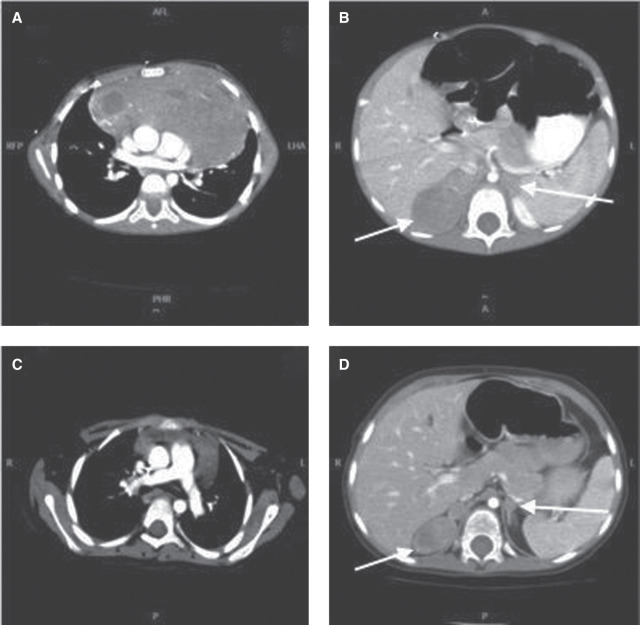

T-lymphoblastic lymphoma (T-LLy) is the most common lymphoblastic lymphoma in children and often presents with a mediastinal mass. Lymphomatous suprarenal masses are possible but rare. Here, we discuss the case of a previously healthy 3-yr-old male who presented with mediastinal T-LLy with bilateral suprarenal masses. Following initial treatment, surgical biopsy of persisting adrenal masses revealed bilateral neuroblastoma (NBL). A clinical genetics panel for germline cancer predisposition did not identify any pathogenic variants. Combination large panel (864 genes) profiling analysis in the context of a precision oncology study revealed two novel likely pathogenic heterozygous variants: SMARCA4 c.1420-1G > T p.? and EZH2 c.1943G > C p.(Ile631Phefs*44). Somatic analysis revealed potential second hits/somatic variants in EZH2 (in the T-LLy) and a segmental loss in Chromosome 19p encompassing SMARCA4 (in the NBL). Synchronous cancers, especially at a young age, warrant genetic evaluation for cancer predisposition; enrollment in a precision oncology program assessing germline and tumor DNA can fulfill that purpose, particularly when standard first-line genetic testing is negative and in the setting of tumors that are not classic for common cancer predisposition syndromes.